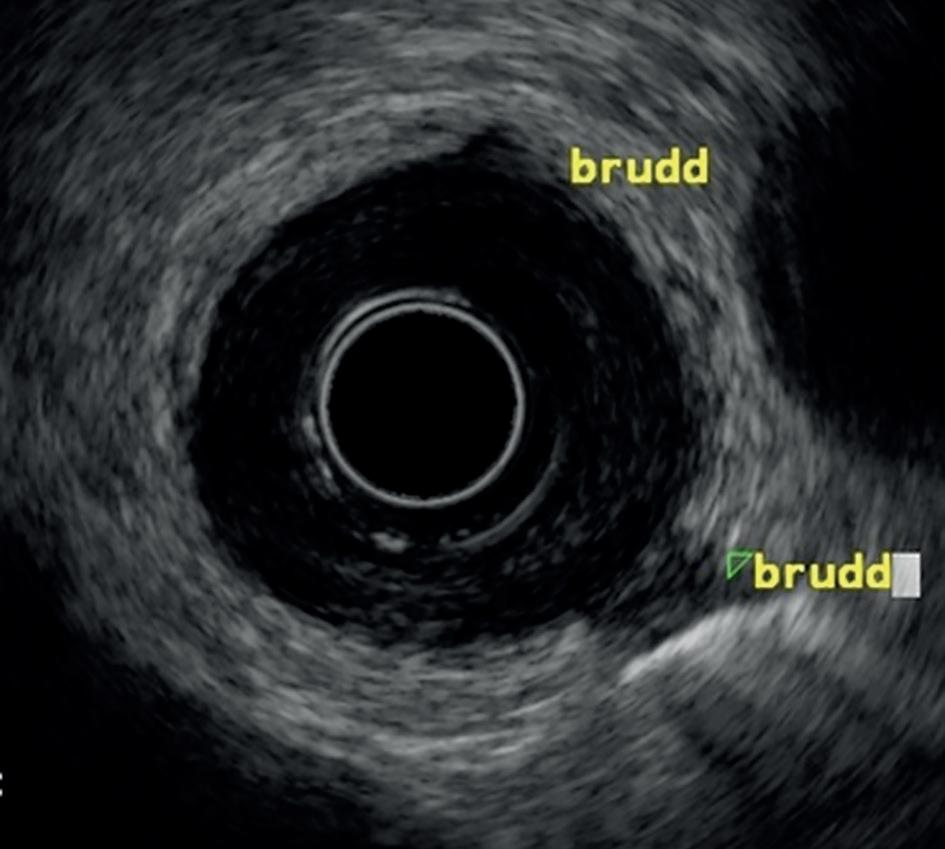

Fra 1980-årene ble den første generasjonen skop med radial skanning utviklet og tatt i klinisk bruk ved en del sentre. Radielle skop gir et UL-plan som går ut fra skopet i midten og vanligvis gir en 360 graders sektor (figur 1). De egner seg for avbildning av sirkumferensen i GI-traktus og organer like utenfor denne, som lymfeknuter i mediastinum og pankreas. Samtidig startet utviklingen av miniprober som ga radielle bilder med høyere UL-frekvens, og dermed høyere detaljrikdom, men kortere rekkevidde. Disse kunne føres gjennom arbeidskanalen på ordinære gastro- og koloskop, nærmest slik man fører inn en biopsitang. De gav god avbildning av tarmveggens ulike lag og ble brukt til å avgjøre om en tumor var intramural eller ekstramural, evt. om den bare var en del av submukosa. Bruken av miniprober er i dag et avsluttet kapittel. Per i dag er de de lineære ekkoendoskopene med relativ stor arbeidskanal på ca. 3,6-4,0 mm som dominerer EUS-aktiviteten. Instrumenter som føres gjennom arbeidskanalen vil derfor være synlig i sanntid på ultralydbildet samtidig som de er synlige i det endoskopiske bildet (figur 2). Lineære skop har vanligvis skrå optikk, på ca. 50 grader, som gjør nedføring teknisk noe vanskeligere enn ved radielle skop. I tillegg vil ultralydproben forlenge den stive tuppen av skopet, og øke risiko for skade og perforasjon av veggen i GI-traktus, spesielt i duodenum. Det er imidlertid svært få rapporterte komplikasjoner i forbindelse med EUS-undersøkelser i Norge.

Figur 1.

A: Radielt EUS skop med 360 graders sektor avbildning i et plan vinkelrett på skopets lengdeakse. B: Radiell EUS (2012) av øsofaguscancer med fortykket vegg ca. 7 mm uten gjenkjennelige vegglag. Tumor vokser i hele cirkumferensen og det sees to gjennombrudd til adventitia, hvor det ene går ut mot pleura nede til høyre (uT4). (Bilde: R.F. Havre)